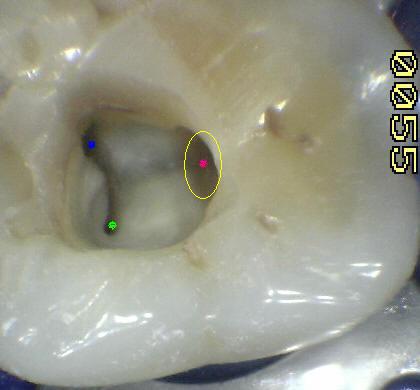

Observe en la

imagen superior la dentina secundaria de

color blanca que obstruye la entrada de los

conductos. Imagen X10 cámara intraoral. |

|

Tres

conductos en piso de cámara pulpar, el conducto

distal se encuentra ensanchado en sentido

buco-lingual, debe sospechar la existencia de

dos conductos que comparten el orificio de entrada.

Cámara intraoral X10 aumentos. |

| 1º Molar

inferior: El orificio de entrada del

conducto distal se encuentra ensanchado

en sentido buco lingual, debe sospechar

la existencia de un cuarto conducto.

La localización

de un cuarto conducto se lleva a cabo

con la

técnica radiológica de Clark

o por

medio de una lima curvada en distal para

sondear la pared lingual ó vestibular

del conducto distal. Imagen inferior |

DS:

dentina secundaria de color más claro. Cámara

intraoral X10 aumentos. |